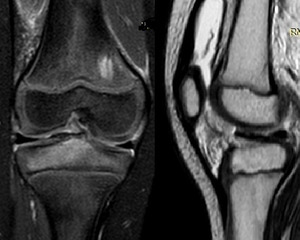

Plain anteroposterior and lateral radiographs demonstrated a bony fragment detached from the tibial plateau at the level of the tibial spine, consistent with a partially displaced, but not rotated, ACL avulsion fracture (Figure 1). The fracture was classified as a Type II Meyers and McKeever lesion based on radiographic features. Magnetic resonance imaging (MRI) confirmed the diagnosis, showing avulsion of the tibial spine with a fragment arising from the tibial eminence, associated bone marrow edema, and soft-tissue swelling. No meniscal tear or intermeniscal ligament entrapment, chondral lesion, collateral ligament injury, was detected (Figure 2).

After multidisciplinary discussion, and considering the absence of concomitant soft-tissue pathology on MRI, a conservative approach was selected. Treatment consisted of immobilization with a long-leg cast in full extension for 30 days with strict non-weight bearing (Figure 3).